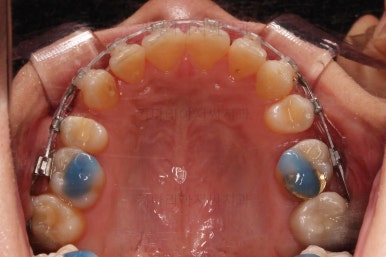

4. 마무리

할 수 있는 부분과 수용한 부분을 구분해서 환자분과 적절히 치료계획을 타협하고요. 치료를 마무리합니다.

가지런한 느낌 좋고요.

교합도 잘 맞고 이 뽑은 자리도 틈이 없으며 사랑니 당겨온 자리도 틈새 없이 잘 마무리가 되었네요.

다만 앞니가 예전에 부러져 있어서 형태저긍로 조금 부족하긴 했지만 나쁘지 않았습니다.

연산동교정치과 전후 비교해 보겠습니다.

전반적으로 깔끔하게 임플란트 없이 결손치아 부분을 잘 마무리 했습니다.

이상 결손치아가 있을 때 미니스크류를 이용해 임플란트 없이 사랑니를 당겨와 치료한 연산동교정치과 치료사례였습니다.